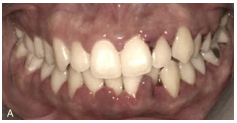

Analise a imagem abaixo para responder à questão 28.

(Carranza 2016).

A imagem demonstra uma garota de 13 anos de idade com inflamação papilar e marginal exacerbada por hormônios, com profundidade de bolsa de 1 a 4 mm, com mínima perda de inserção clínica, portanto, é correto afirmar que a avaliação foi feita por uma vista